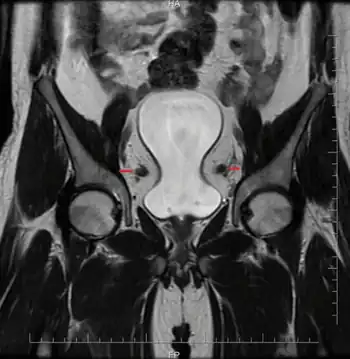

| MRI pelvis shows pelvic lipomatosis compressing the bladder and ‘eye’ formed by dilated vas | |

Pelvic lipomatosis is a rare disease that is most often seen in older obese black men with hypertension. In pelvic lipomatosis, abnormally dense deposits of otherwise apparently normal fat may be observed in the spaces of the pelvic area.[1]

It is associated with cystitis glandularis, a precursor to adenocarcinoma of the urinary bladder. It is associated with deposition of mature unencapsulated fat in the retroperitoneal pelvic space producing the typical "pear-shaped" appearance of the bladder on CT scan. This condition also causes a straightening and tubular appearance of the rectum.